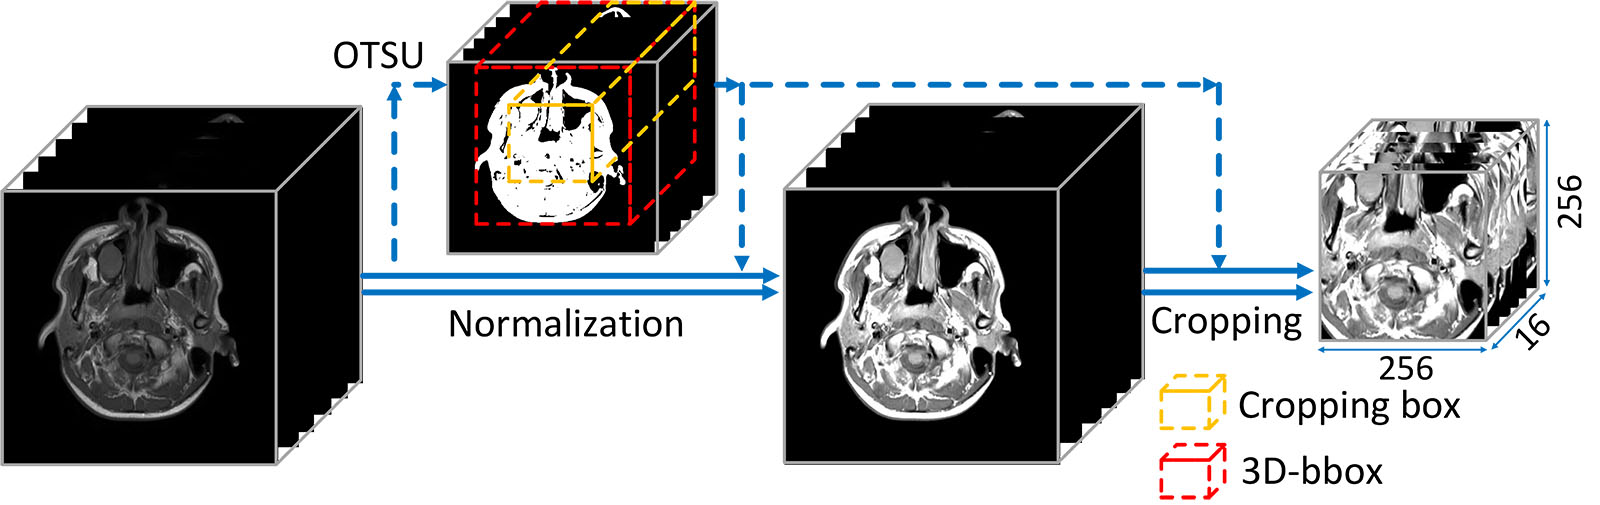

Preprocessing. The preprocessing mainly contains intensity normalization and ROIs cropping. We utilize the intra-body intensity normalization proposed in [43], which effectively deals with the differences caused by imaging configurations and the influences of inconsistent body-to-background ratios. After normalization, according to the distribution histogram of normalized data, we clip (limit) values to reduce the complexity of data. Through statistical analysis for values in NPC regions, we set , and for T1, T2 and CET1 respectively.

We use a sliding window to crop ROIs and feed them into network. Specifically speaking, we firstly use OTSU to get the 3D bounding box (3D-bbox) of original MRI and then we crop a region according to the central point of 3D-bbox. The sliding window slides on the Z axis and the sliding-step is 4. When feeding training samples, we perform on-the-fly data augmentation. Operations including random central offset from to , random vertical flipping and random rotation on the XY plane from to are applied. The illustration of preprocessing is shown in Figure 6.